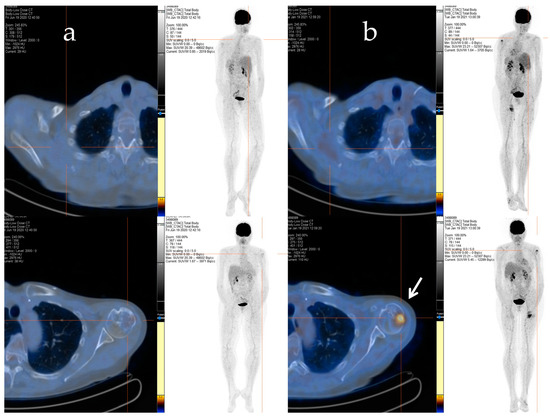

Afterwards, radiation therapy to the cervical segment (C4–C6) and left humerus (20 Gy/5 fractions) was performed, and a chemotherapy regimen consisting of epirubicin and ifosfamide was started. Despite an initial positive response after six cycles of treatment, signs of bone and soft tissue progression were apparent three months after the chemotherapy ended. Thus, the patient received a second-line treatment with trabectedin (1.5 mg/m2 q21), which was administered as a 24 h infusion every 3 weeks. After 48 cycles of treatment, despite the stable disease, the patient decided to discontinue the treatment due to severe fatigue, and a close follow-up was started. The patient maintained stable disease until January 2021 when a PET/CT scan revealed an increased uptake in the left proximal humerus (Figure 2a,b), right scapula, sternal manubrium, right iliac bone, and ipsilateral acetabulum.

Figure 2.

The F-18 FDG PET/CT performed after 48 cycles of trabectedin treatment (a) and after the period of trabectedin suspension (b). The main tumour lesions are indicated by white arrows.

With the rising of the disease, trabectedin treatment was resumed and continued for an additional 21 cycles until January 2022, when a PET/CT scan revealed a slight metabolic progression in the left humeral head. Thus, in March 2022, radiotherapy treatment on the left humeral head was completed (20 Gy/5Fractions), and, considering the stable disease revealed in July 2022, the trabectedin administration was continued until February 2023 (Figure 3).